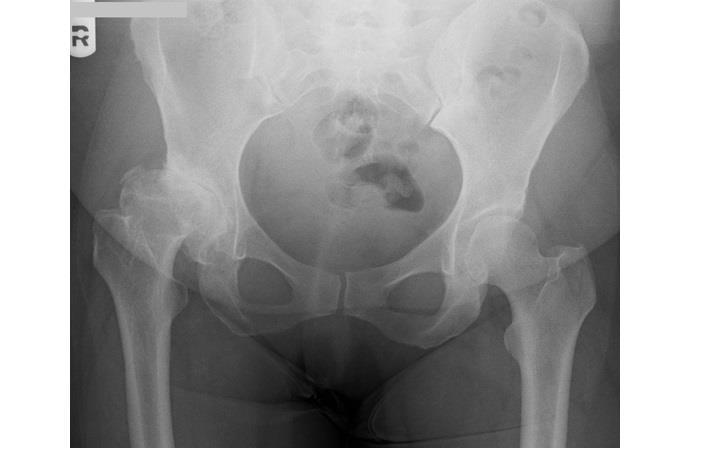

ניתוח החלפת מפרק ירך מתאים למטופלים הסובלים מכאבים ממושכים באזור המפרק שלא הוקלו למרות ביצוע של טיפולים שמרניים. ברוב המקרים, מדובר בכאב כרוני אליו נלוות תלונות כמו פגיעה בטווח התנועה והגבלה משמעותית בתפקוד. הסיבה השכיחה ביותר לפגיעה במפרק הירך היא שחיקת סחוסים. אולם, קיימים גם מצבים אחרים העלולים לגרום לפגיעה במפרק, כמו למשל מחלות דלקתיות כגון דלקת מפרקים שגרונית, מצבים לאחר חבלות ושברים, נמק של ראש הירך ואחרים.

חשוב לציין כי כאבים באזור המפרק אינם בהכרח מעידים על צורך בניתוח להחלפת מפרק הירך. אם מדובר בכאב שמוקרן מעמוד השדרה, אם קיימת דלקת בבורסה הטרוכנטרית (דלקת בגיד המחובר לאזור מפרק הירך, אך איננו מערב את המפרק עצמו), אם התפתחו קרעים בגידים וברצועות סביב מפרק הירך אשר אינם מערבים את המשטח הסחוסי וכן גם אם אובחן מצב אשר גורם לכאב שעשוי לחלוף תוך מספר שבועות (לדוגמה – transient osteoporosis, בצקת חולפת במפרק הירך האופיינית לגברים בגיל העמידה ונשים בהריון, גורמת לכאבים עזים במפרק אשר חולפים לחלוטין תוך חודשיים – שלושה), אין צורך בביצוע הניתוח.